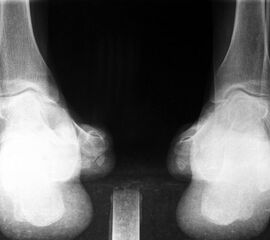

• Ätiologie ungeklärt (Abb. 8 bis 10)

Zum Lesen der Bildbeschreibung und zur Vollansicht bitte die Bilder anklicken. Bilder: A. Simon